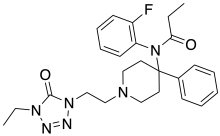

Anilidopiperidines

Phenylpiperidines

The first fully synthetic opioid was meperidine (later demerol), found serendipitously by German chemist Otto Eisleb (or Eislib) at IG Farben in 1932.[228] Meperidine was the first opiate to have a structure unrelated to morphine, but with opiate-like properties.[199] Its analgesic effects were discovered by Otto Schaumann in 1939.[228] Gustav Ehrhart and Max Bockmühl, also at IG Farben, built on the work of Eisleb and Schaumann. They developed "Hoechst 10820" (later methadone) around 1937.[230] In 1959 the Belgian physician Paul Janssen developed fentanyl, a synthetic drug with 30 to 50 times the potency of heroin.[211][231] Nearly 150 synthetic opioids are now known.[228]